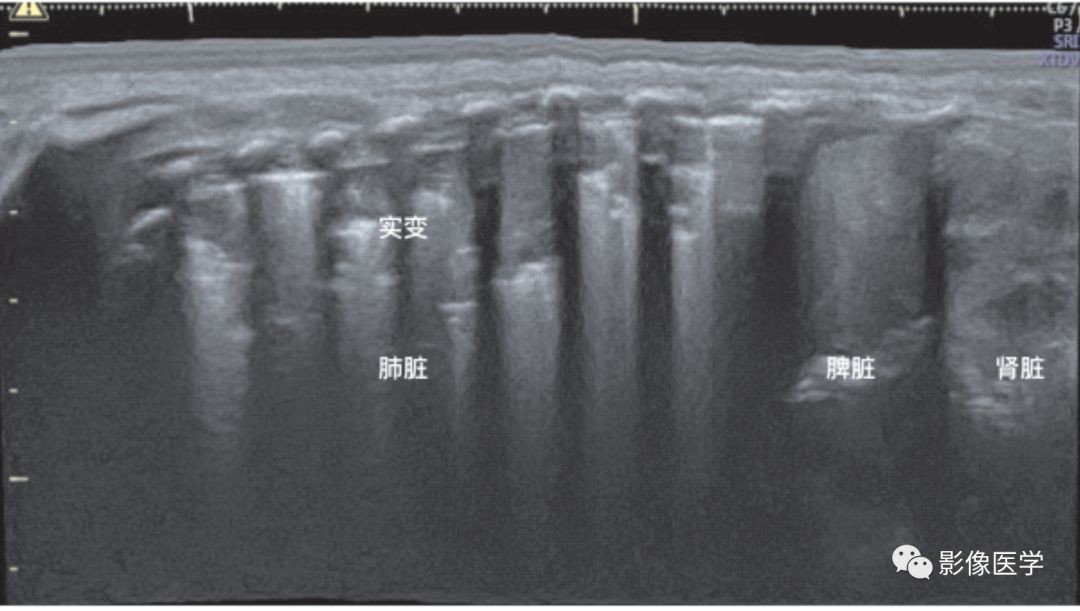

图6-29 肺炎的超声表现:宽景成像模式(1)

肺炎的超声表现(左肺肺炎)——宽景成像模式,依次显示肾脏、脾脏和肺脏。从超声影像上可以看出,几乎左肺在每个肋间均见明显实变伴支气管充气征,每个肋间受累的程度不同。